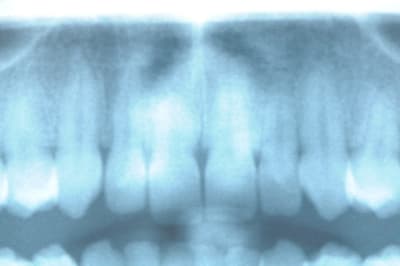

La patiente vient de me donner son unique OPT qui date de 2001

à vous de juger...

pour ceux qui ont un peu de mal à lire la radio, j'ai calculé qu'il y avait une perte d'environ 30% de la longueur de la racine depuis 2001.

ça laisse songeur.